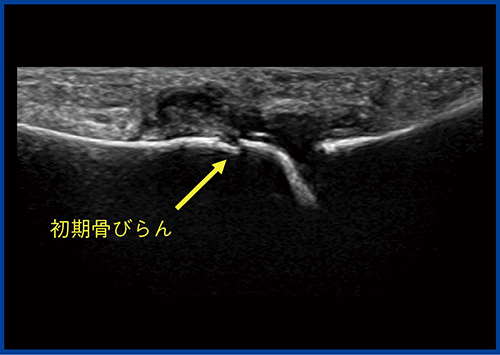

症例2は,Bモードにて中足骨と基節骨の関節の腫れと,関節液の貯留が確認され,一部に初期の骨びらんが疑われた(図5)。カラードプラ(図6)では,滑膜には豊富な血流が見られるが,骨びらんが疑われる部位にはほとんど血流が認められなかった。一方,SMI(図7)では,骨びらんの周囲から骨の中に流入する血流がわずかに認められた。

図5 症例2:第2趾MTP関節炎のBモード画像